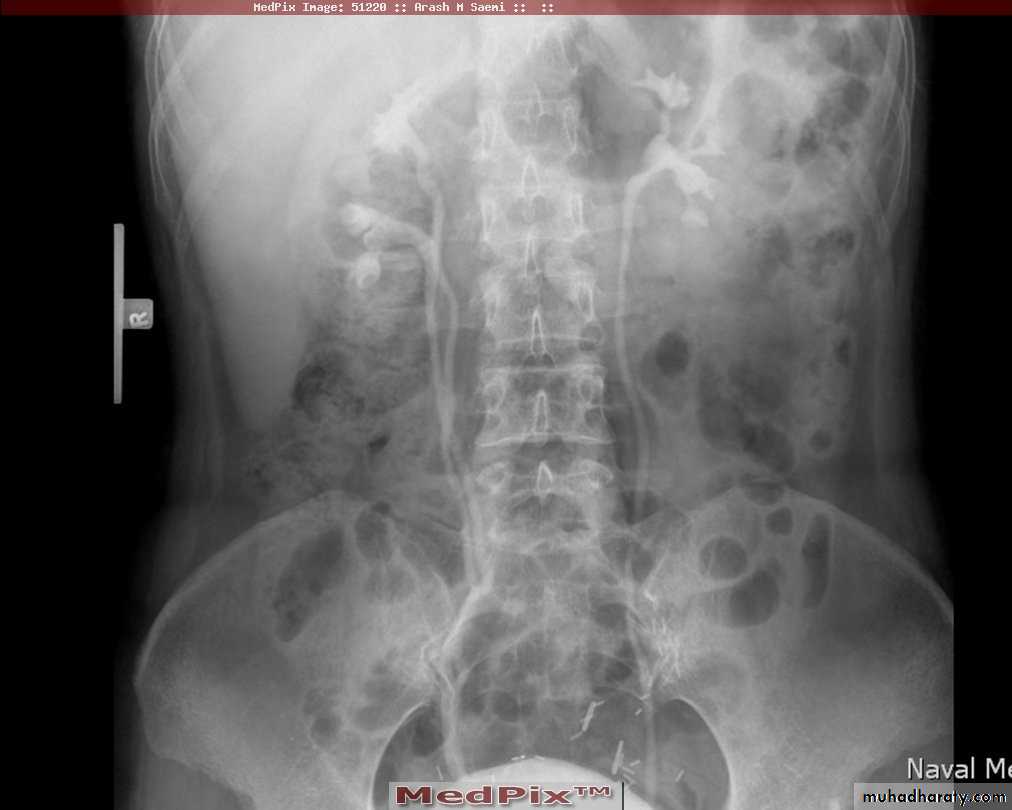

Poly cystic disease

Adult type

Present after the third decade of life , Familial.

Renal parenchyma is replaced by numerous cysts containing fluid , The cysts are of variable size ,

Clinically renal colic, loin mass , heamaturia and hypertension, Renal tissue interposed between the cysts after time dssimcted ended with renal failure

Almost bilateral.

IVU

Large kidney .

Lobulated out-line.

Distortion of pelvi- calyceal system depend on cyst size, number and position.

In advanced cases there is elongation and stretching of minor and major calyces ( spider leg).

In advanced cases IVU shows non-functioning kidney .